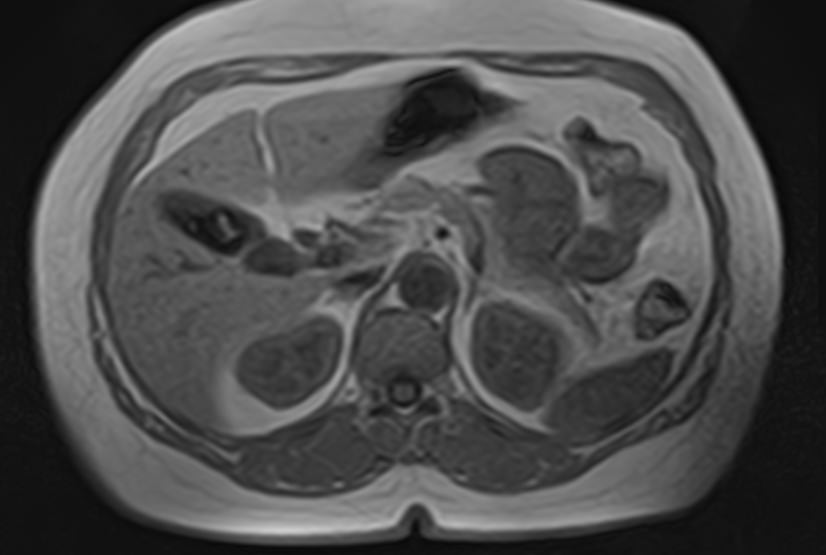

Магнитно-резонансная холангиография – это неинвазивный и безопасный метод исследования, который используется для визуализации желчевыводящих путей, включая внутри- и внепеченочные желчные протоки, панкреатический (Вирсунгов) проток и общий желчный проток (холедох). МРТ позволяет оценить анатомические особенности билиарной системы и определить патологию расположенных рядом структур.

Патология билиарной системы проявляется в виде непроходимости желчных протоков и затруднением оттока желчи. Нарушение отделения желчи может быть вызвано наличием камней, развитием объемного образования внутри протока или сдавлением протока опухолью извне.

С помощью магнитно-резонансной холангиографии можно выявить следующие патологии:

- Острое или хроническое воспаление панкреатобилиарной системы;

- Закупорка протоков конкрементами;

- Доброкачественные и злокачественные опухоли внутри просвета протоков или новообразования, исходящие из окружающих тканей;

- Рубцовые деформации, спайки, стриктуры желчевыводящих путей.

- Аномалии развития желчевыводящей системы.